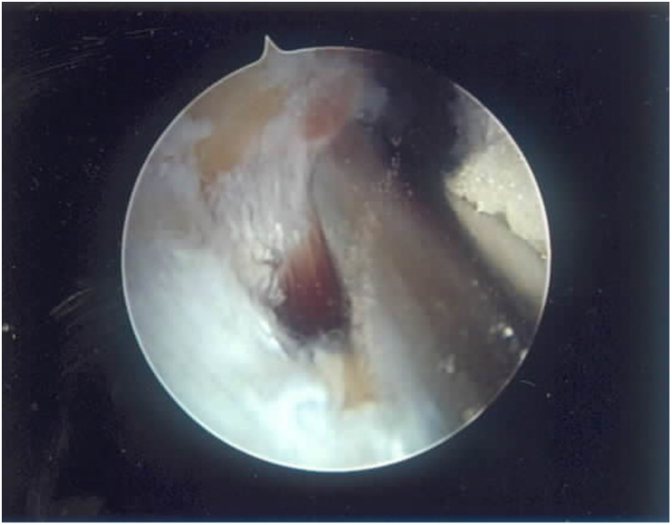

Fig. 5A.

This view from a posterior lateral portal with a 70-degree arthroscope shows an osteochondritis dissecans of the capitellum (above), with an inflamed plica laterally and the intact radial head below.